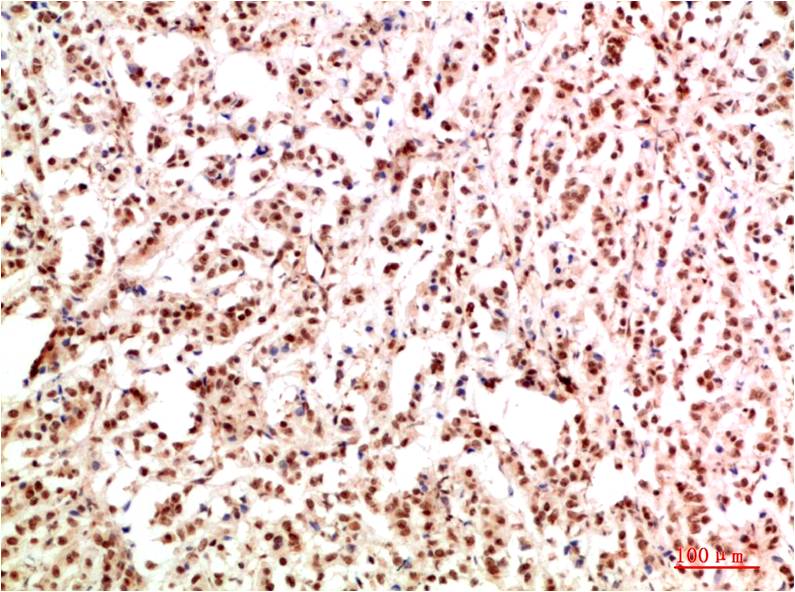

Gab1 Rabbit Polyclonal Antibody

Catalog NO.:BE3744

Applications :IHC

Reactivity :H,R,M

Recommended dilutions: IHC: 1:200-500

Specificity: The Gab1 Rabbit Polyclonal Antibody can detects endogenous Gab1 proteins.